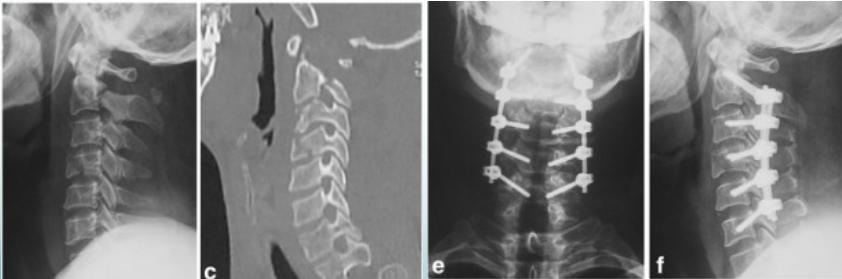

Cervical Burst Fracture

- Axial compression

- Diving

- Unstable

- Neurological injury

http://www.learningradiology.com/

Fracture-Dislocation

- Secure stabilization:

- Skin / Skeletal Traction

- Surgery +/- Decompression